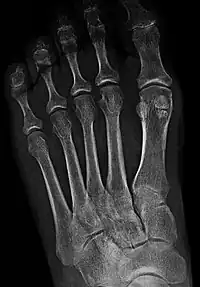

Un hueso sesamoideo es un hueso pequeño y redondeado incrustado en un tendón sometido a compresión y a fuerza de tensión habituales. Los huesos sesamoideos se encuentran en diversas articulaciones del cuerpo.

En los miembros superiores normalmente se hallan en la articulación de la cara palmar de la mano. Los dos más comunes están en los tendones de las dos porciones del flexor corto del pulgar, en la articulación metacarpofalángica. En los miembros inferiores el sesamoideo de mayor tamaño es la rótula. Otro sesamoideo situado en la parte posterior de la rodilla es la fabela, localizado en el espesor del tendón del gemelo externo, y que en ocasiones puede confundirse con un cuerpo libre interarticular. Los huesos sesamoideos, además de en las articulaciones, pueden hallarse en los tendones del miembro superior, o a veces en el tendón del bíceps braquial, también se observan en los tendones de las extremidades superiores. En algunas situaciones se produce inflamación a nivel de los hacecillos, principalmente en la base del dedo gordo, produciéndose una sesamoiditis.